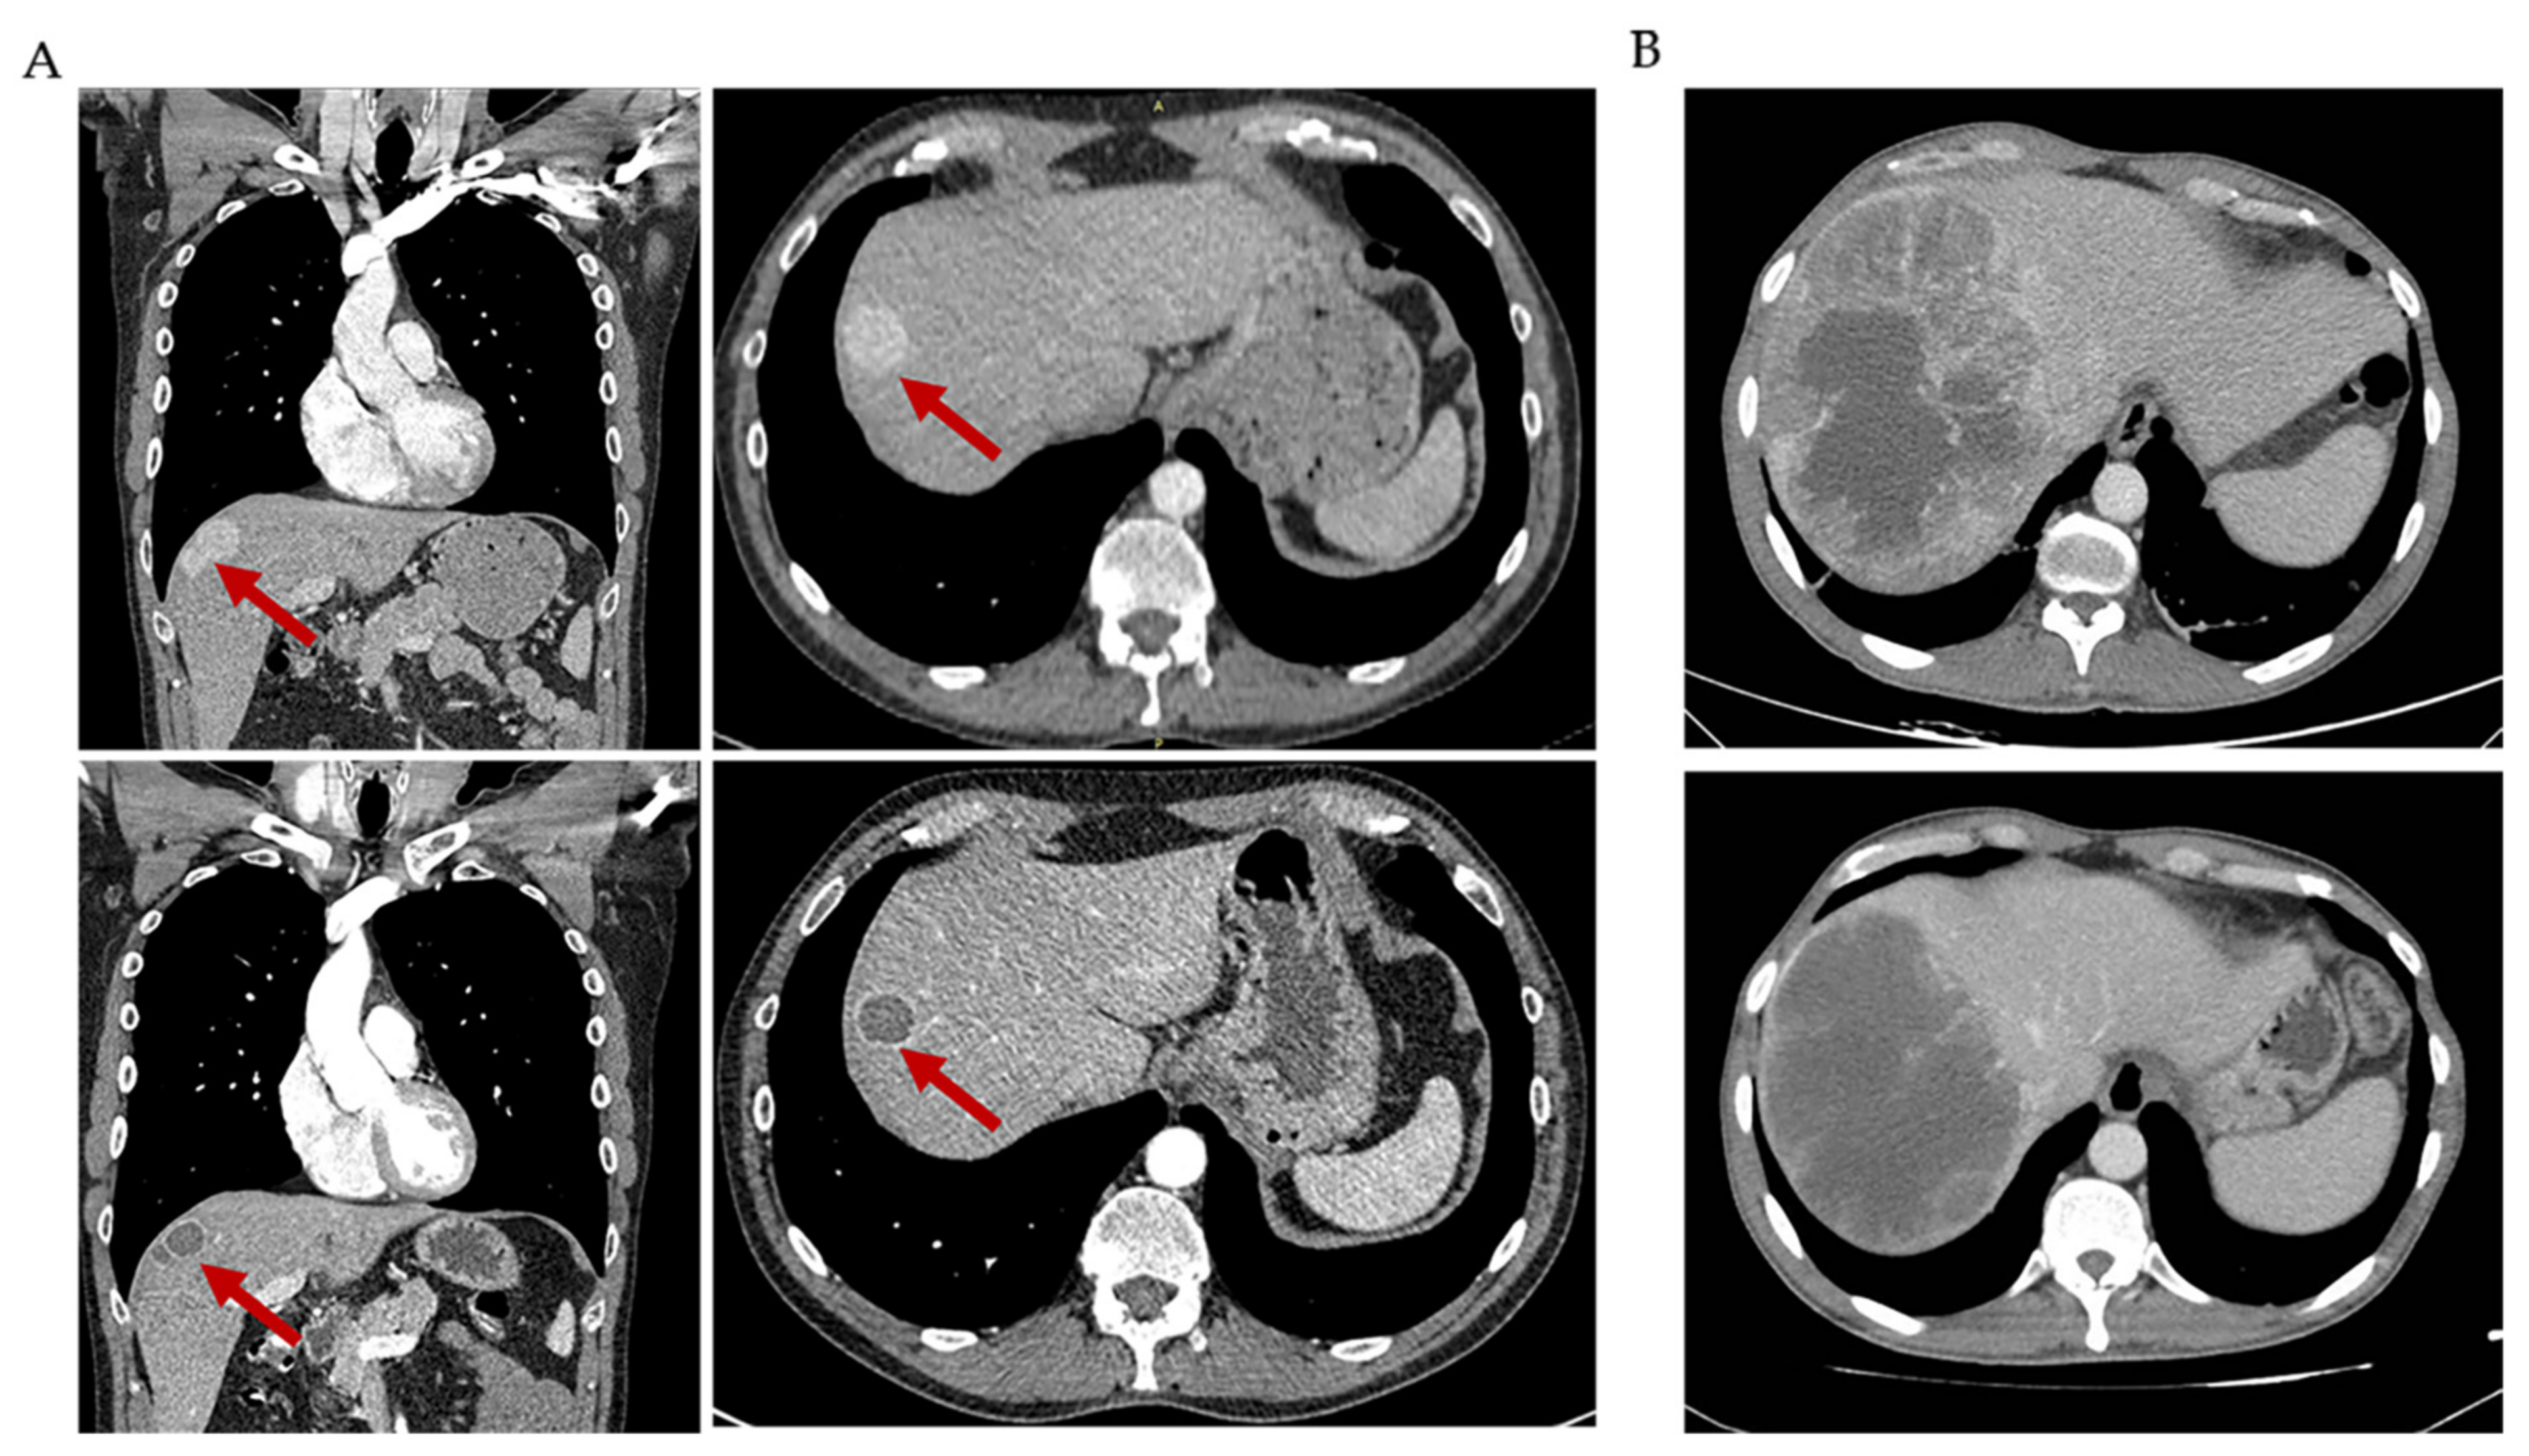

2.2. Radiological Characteristics